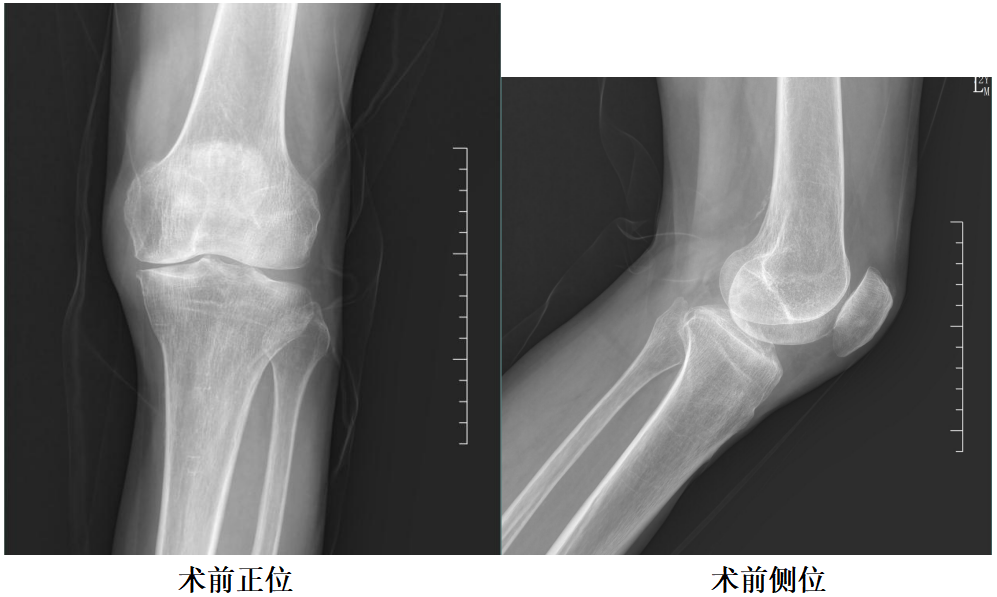

X-Ray:左膝内侧间隙明显狭窄,站立位内侧间隙消失,外侧间隙正常,膝关节稳定。

二、术前X片